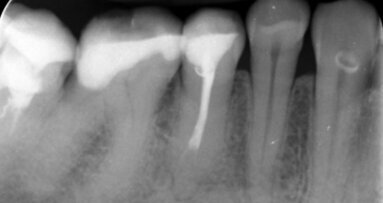

_chroniczne zapalenie przyzębia (Ryc. 3a i b), które rozwija się po 45 r.ż.

Radiografia obu klinicznych sytuacji obrazuje zaawansowany etap choroby. Te 2 przypadki różnią się przede wszystkim wiekiem pacjenta, który ma 25 lat w przypadku agresywnego zapalenia przyzębia (Ryc. 2a i b) i 68 lat w przypadku chronicznego zapalenia przyzębia (Ryc. 3a i b).